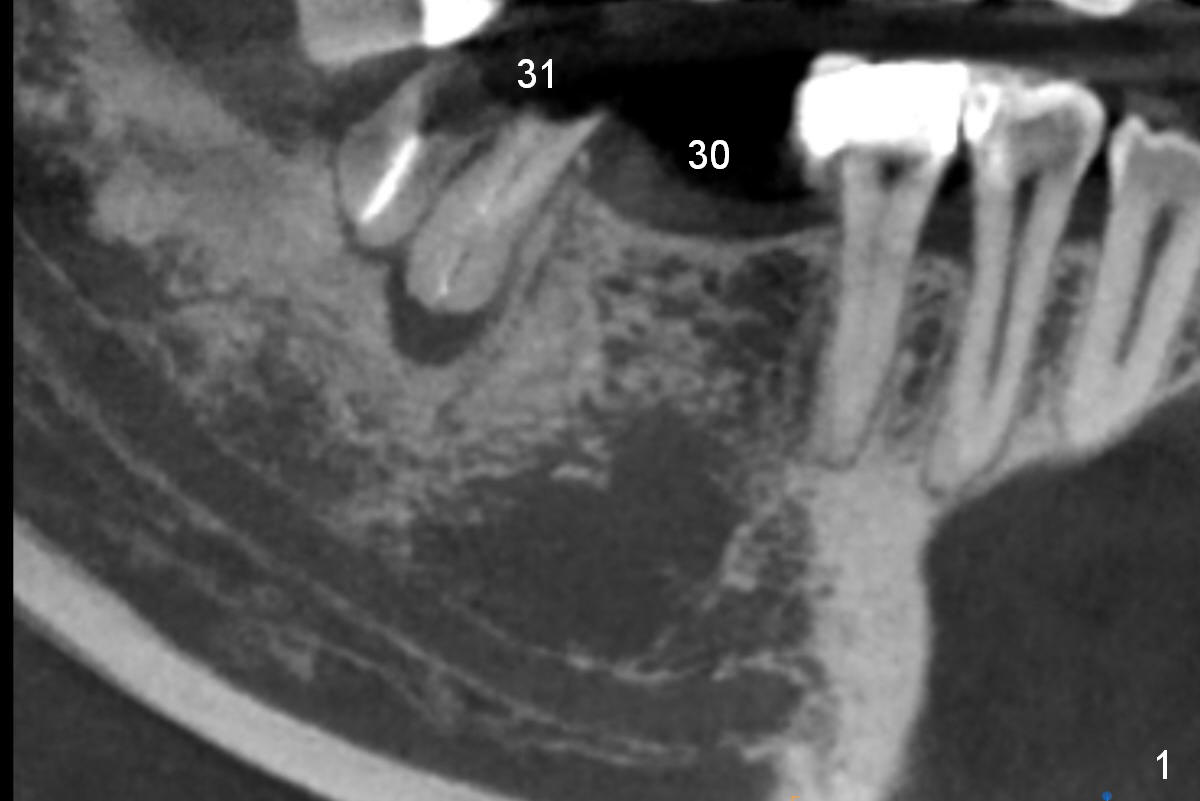

A 47-year-old woman has had 3 bridges. One of them (the lower right) is broken down. The patient requests removing the tooth #31 (Fig.1 CBCT), because of difficulty in keeping it clean. Since the buccal plate is thin (Fig.2 (axial section), 3 (coronal section) >) or absent (Fig.2 *), a 5 mm implant will be placed lingually (Clindamycin). Tap will be used prior to implant placement.